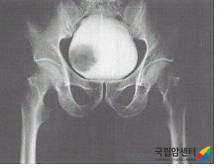

[ 방광암의 배설요로조영술 소견 ]

신우에서 방광까지의 요로를 관찰하여 혈뇨의 원인을 찾기 위해 배설요로조영술을 시행합니다. 방광에 암이 생긴 경우에 요로상피로 덮여 있는 신우와 요관에도 2~3% 정도에서 암이 발생할 수 있으므로 신우와 요관의 병변 유무를 확인하기 위해 배설요로조영술(IVP, 경정맥 신우 조영술)을 시행하기도 합니다.